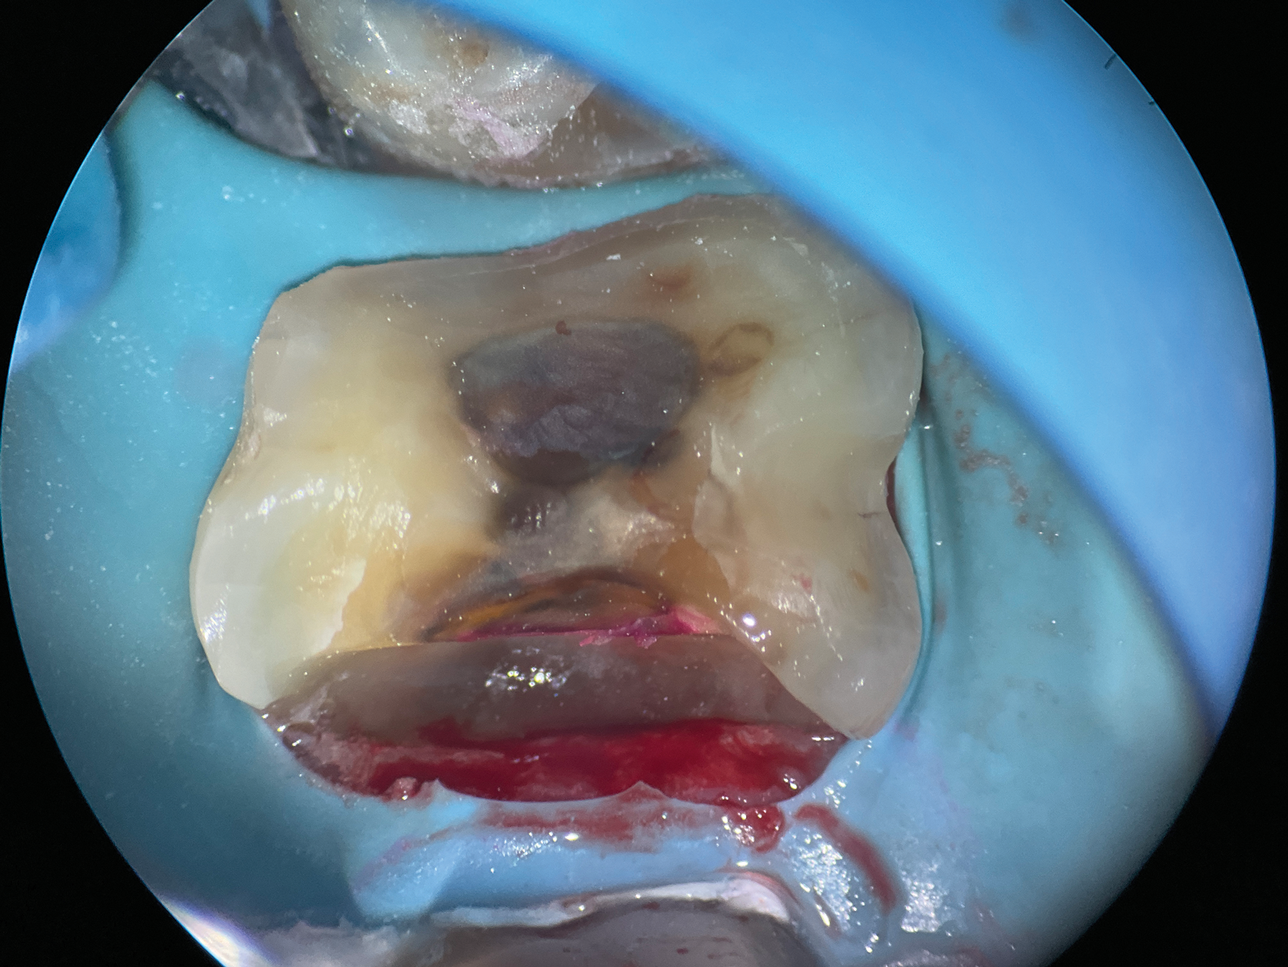

(8.) Close-up occlusal view of a maxillary first molar after the removal of deep subgingival caries, where despite rubber dam isolation, infiltration of blood and saliva into the cavity has occurred.

Figure 8

(9.) Close-up occlusal view of the maxillary first molar prepared for a matrix-in-matrix technique with a circumferential matrix supported by a 3-mil copper band inside for proper adaptation to the margin’s concave and convex areas. Note the addition of a liquid dam material placed between the two matrices for added stability.

Figure 9